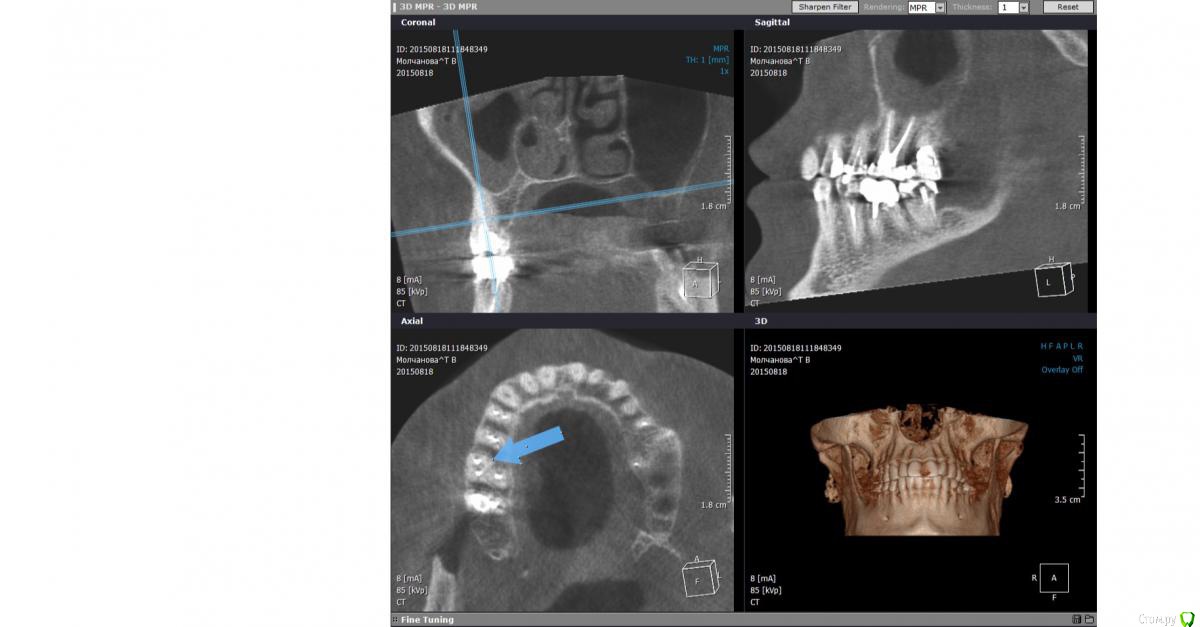

ТаняМ Опубликовано 31 октября, 2015 Поделиться Опубликовано 31 октября, 2015 Добрый день! Женщина, 41год. Истрия длится почти 8 месяцев. Заболела верхняя то ли 7 то ли 6 справа. На рентгене ничего подозрительного. 4 и 5 мёртвые давно. Долго не буду рассказывать, в общем каналы 6,7 также почистили и запломбировали. Очень долго болели опять же непонятно какие из них. Врач сказала, что проблемы со связками там есть, очистила ультразвуком несколько раз. Все прошло до июля. Опять начали ныть то ли 5,6 то ли 7. Чуть припухло около носа. Рентген-все чисто. Зачем то депульпировали нижнюю 4, врач решила, что это отраженные боли. Бестолку. Вскрыли 7 - чистили каналы, было дико больно, положили лекартство. Толку 0. Послали на КТ. Увеличина слизистая с правой стороны. Без жидкости. По зубам сказали все ОК. Сказали гайморит. Хотя никаких выделений из носа. Пропила антибиотики, промывания - толку 0. Боли сильные. Пошла к другому врачу. Вскрыли и 6. Опять прчистили все каналы, положили такую пасту коричневую - как смола и о чудо! Боли проходят, припухлость спадает. На простом пленочном рентгене увидели воспаление на 6, хотя КТ его не показало. Ходила 4 недели, меняли лекарство. На последнем (с камфорой) опять стало поднывать. Врач пломбирует каналы 7. Все ок. Не болит. Через неделю, проверяет каналы 6, говорит все отлично, каналы сухие, здоровые, плобирует каналы 6. При пломбировке было больновато. На след. день опять ноющая боль и небольшая припухлость. Короче, прошло 3 недели. Сильные боли опять то ли 7,6,5? Утром встаю прямо как жидкость возле носа справа. И боль щека, нос справа. Боль отдаёт в челюсть, под глаз, ухо. На десне в проекции этих зубов как болячка небольшая. Болит очень голова постоянно. Рентген пазух, осмотр Лора - гайморита нет. Рентген 6,7 - пломбировка отличная. Просила открыть 6-ку. Колят траумель в десну и говорят, что больше туда не полезут, только если удалять зубы, т.к. с их стороны ничего не видят и сделано по максимому. Оба зуба, забыла сказать, корнями находятся в гайморовой. Что мне делать? Это какой-то 3-х месячный ужас. Что посоветуете? Спасибо большое. Снимки после пломбировки прилагаю. Ссылка на комментарий

ТаняМ Опубликовано 31 октября, 2015 Автор Поделиться Опубликовано 31 октября, 2015 Вот на всякий случай скрины КТ до повторных перепломбировок. Может там тоже что-то увидеть можно? Ссылка на комментарий